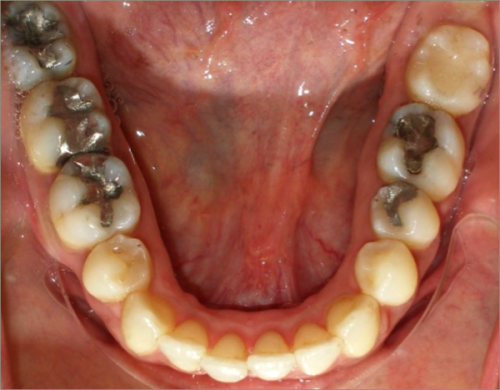

32 year old female:

Diagnosis:

- Previously lost upper first molars

- Severe lower arch crowding

- Midline discrepancy

- Narrow upper arch form

Treatment:

- Extraction of lower right first bicuspid

- Substitution of upper second molars for first molars

- Full fixed appliances

- 23 months